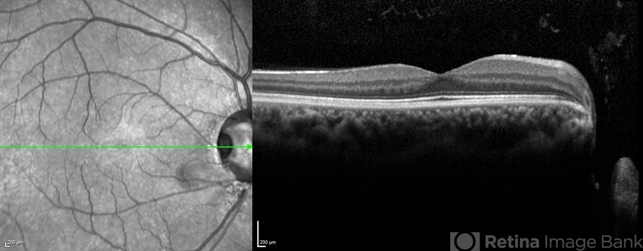

Optical coherence tomography system

Heidelberg Spectralis - Description

- SD-OCT of the right eye of a 26 year man revealing Optic disc pit .